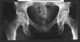

Degenerative change

Degenerative disc disease (DDD) is a medical condition in which there are anatomic changes and a loss of function of varying degrees of one or more intervertebral discs of the spine of sufficient magnitude as to cause symptoms. The root cause is thought to be loss of soluble proteins within the fluid contained in the disc with resultant reduction of the oncotic pressure, which in turn causes loss of fluid volume. [Source: Wikipedia ]